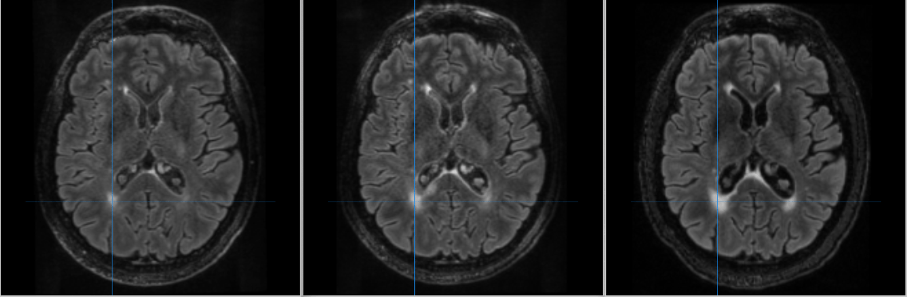

We developed a robust methodology and designed an automated pipeline to quantitatively measure chronic lesion expansion. This pipeline (LEAP: Lesion Expansion and Analysis Pipeline) allows for precise and reproducible evaluation, enabling more accurate tracking of lesion dynamics in individual patients.

We investigated the spatial distribution of chronic lesion expansion, revealing patterns that highlight the variability and focal nature of smouldering inflammation. This work contributes to understanding the heterogeneity of lesion behaviour and its implications for disease progression.